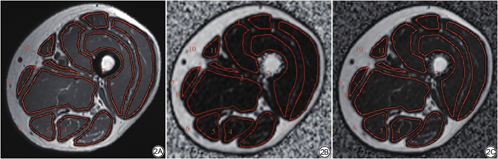

将所有大腿MR扫描图像导入GE后处理工作站ADW4.6,在冠状位上确定大腿中部位置对应的轴位T1WI、脂肪分数图的层数(图1),将T1WI及脂肪分数图进行匹配。由住院医师A在T1WI图像上进行ROI的勾画,勾画过程中ROI距离肌肉边缘1~2 mm,避免将皮下及肌间脂肪勾入ROI内。记录每块肌肉的脂肪分数(fat fraction,FF) (图2)。

所有ROI的勾画步骤如下:所有肌肉/脂肪区域的分割都是由住院医师C手动完成的。①在T1WI图像上进行SAT内外轮廓的勾画,SAT外轮廓为T1WI图像上高信号的最外缘(图3A箭),内轮廓为大腿阔筋膜(图3A箭头);②沿股骨外侧缘勾画包含骨皮质及骨髓腔的区域(图3C箭);③紧贴每块肌肉的边缘勾画出每一块肌肉的轮廓(图3D)。④沿SAT内轮廓剪去所有肌肉及股骨区域即可获得InterMF (图3E,蓝色区域);⑤在SAT内轮廓内剪去InterMF区域及股骨区域即可获得肌肉CSA (图3F);⑥通过ImageJ内的阈值调整使肌肉内肉眼可见的脂肪尽量着色,着色区域即为intraMF (图3黄色)。

基于ImageJ分割测量的IntraMF面积Sintra与基于脂肪分数计算的IntraMF面积Sintra-FF对比见表3。统计结果表明:基于ImageJ分割测量的IntraMF面积与基于脂肪分数计算的IntraMF面积差异无统计学意义(P=0.589)。图4对比了基于ImageJ分割方法的T2DM受试者与正常组志愿者的Sth、Sinter及Sintra。

ImageJ分割测量的IntraMF面积Sintra和Goutallier分级与基于脂肪分数计算的IntraMF面积Sintra-FF的相关性分析见表4;Sintra与Sintra-FF的相关性散点图见图5。结果表明:ImageJ分割测量的Sintra与基于脂肪分数计算的Sintra-FF相关系数r=0.998,差异有统计学意义(P<0.001);Goutallier分级与Sintra-FF无明显相关性(P=0.205)。基于ImageJ分割的大腿Sth、Sinter、Sintra的观察者内及观察者间的一致性分析见表5,结果表明:基于ImageJ分割的大腿Sth、Sinter、Sintra的观察者内及观察者间ICC分别是:0.999、0.992、0.997、0.999、0.941、1.000,差异均有统计学意义(P<0.005)。